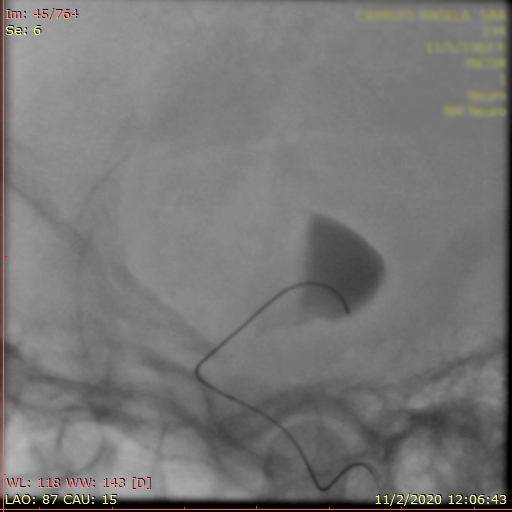

La paciente ingreso al Servicio de Hemodinamia el día martes 11 de febrero con un aneurisma cerebral gigante en la carótida izquierda y se le practicó una embolización; es decir una oclusión por dentro del mismo, donde se colocó un dispositivo denominado coils más un stent diversor de flujo. El procedimiento fue exitoso y contó con la colaboración de médicos neurointervencionistas del Instituto Oulton de la Ciudad de Córdoba.